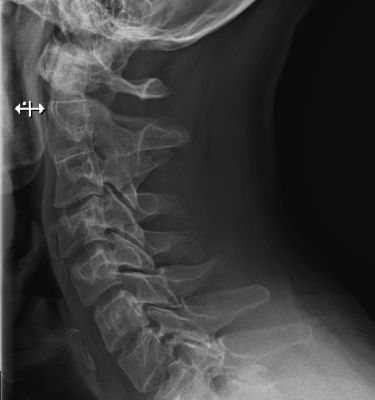

Диагнозы устанавливаются на основе МРТ или КТ шейного отдела, УЗИ сосудов головы и шеи, осмотра врача и проведения тестов.

Для уточнения диагноза может потребоваться консультация ЛОРа, эндокринолога, пульмонолога, травматолога, психиатра и других специалистов. Также могут понадобиться УЗИ щитовидной железы, рентген шеи, флюорография, анализы крови и мочи. При сборе анамнеза можно исключить ненужные обследования и обращения к врачам.

- инструментальную диагностику, включая УЗИ, рентген и КТ.